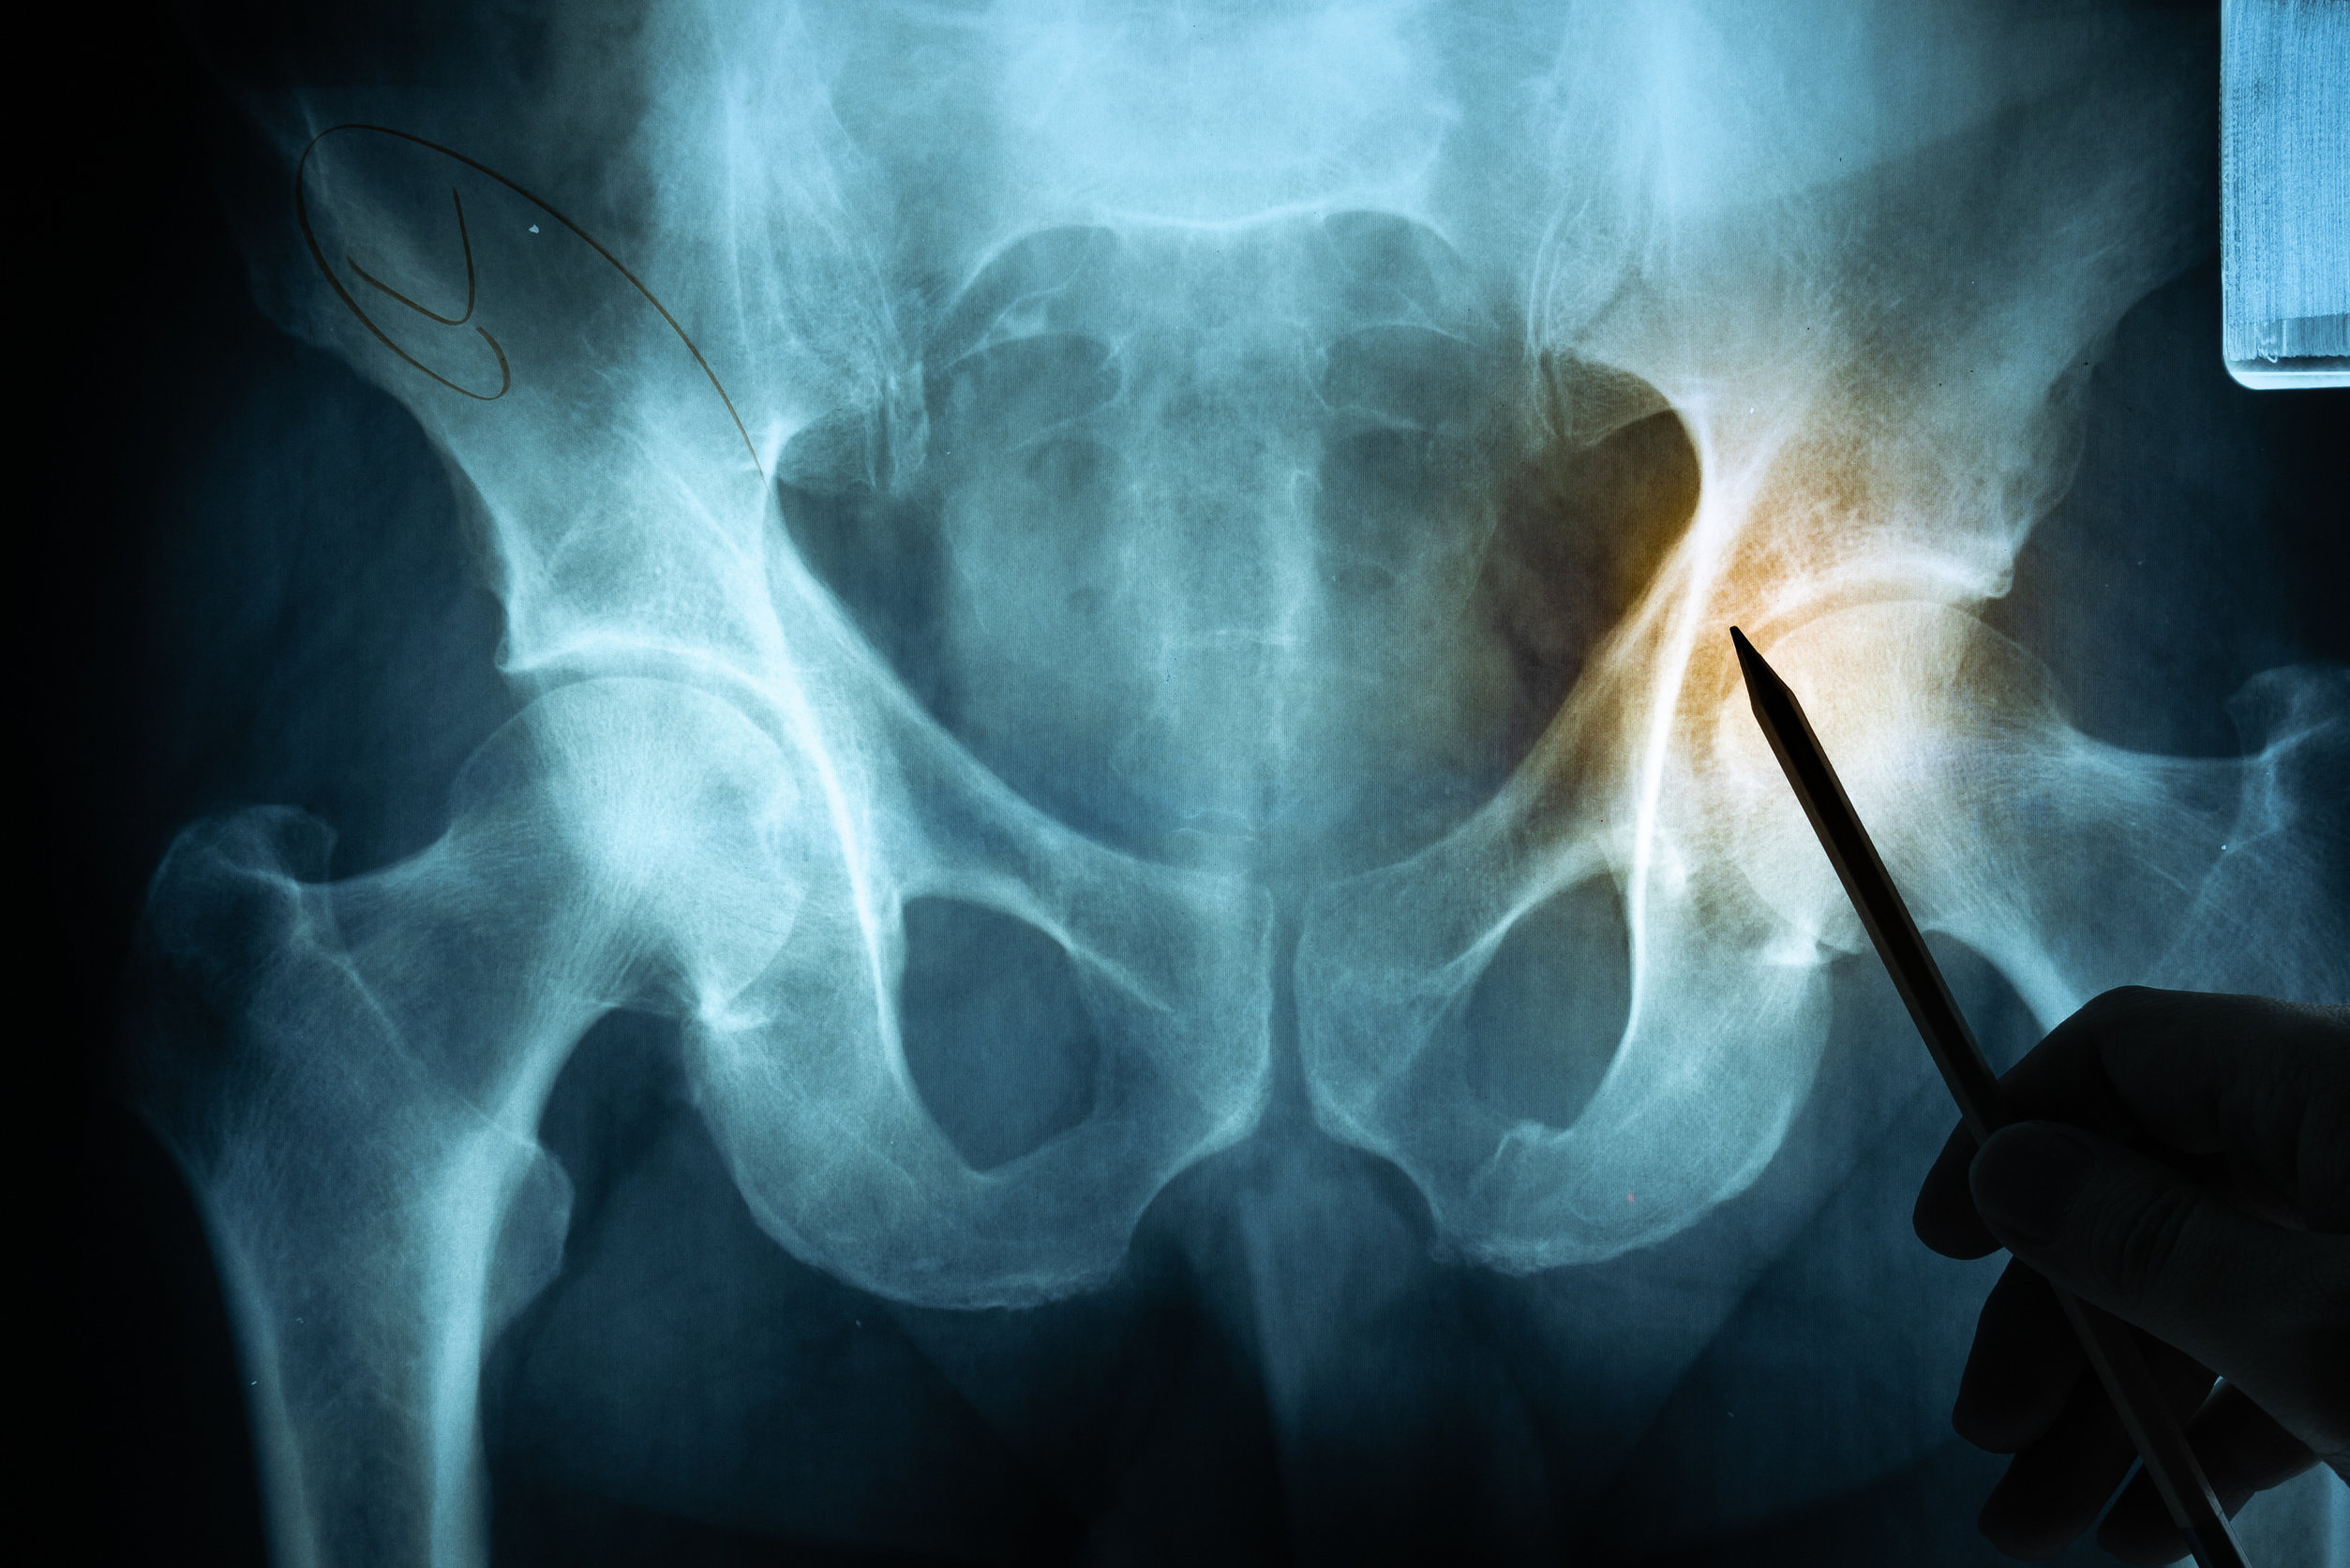

Az ülőideg szervezetünk leghosszabb idege. A medencéből indulva, a csípő-fartájon át fut végig, egészen a combokban majd a térdhajlatban két ágra oszlik. Számos izmot mozgat, és a combok, a lábszárak és a lábak érző beidegződéséről egyaránt gondoskodik. Működési zavara az enyhe érzéskieséstől kezdve egészen a teljes bénulásig, sokféle panasszal járhat.

Az isiász olyan probléma, melynek kiváltó okai változóak lehetnek. Ahogyan fentebb már említettük, okozhatja a gerinc valamilyen problémája, degeneratív betegsége, például a csigolyatestek között elhelyezkedő porckorongok sérve. De az isiász hátterében nemcsak sérv, hanem olyan problémák is állhatnak, mint az ágyéki gerinccsatorna szűkülete, vagy épp a csigolyák közötti ízületek kopása. Sőt, akár gerincen kívüli szervi elváltozás, testi betegség is előidézheti.

A probléma gyakran jelentkezhet a derék és a térd közötti szakaszon, a far belsejétől a belboka irányába futva, vagy a far közepétől a vádli külső felszínén át, egészen a lábfejig. Ezeken a tájékokon a fájdalom, az érzéskiesés és a mozgászavarok egyaránt előfordulhatnak.